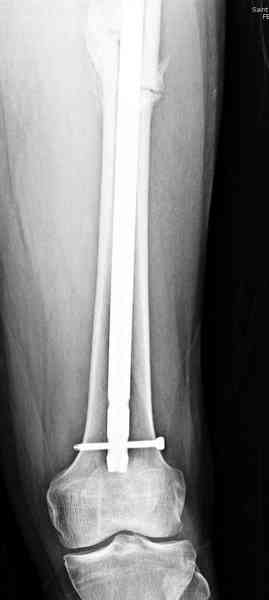

Здесь представлены снимки больного 65 лет, поступившего с диагнозом перелом

бедра после автоаварии.

В первый же день произведено антеградное штифтованием DePuy Trochanteric Nail.

На второй день (7) обнаружен пропущенный перелом,

и проведены шурурпы через и спереди штифта без удаления.

Послеоперационные снимки